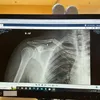

Komika Uus baru-baru ini membagikan pengalamannya setelah terjatuh dari sepeda hingga sepedanya hancur dan tulangnya patah. Setelah kejadian naas itu, ia harus menjalani operasi dan rutin fisioterapi selama sebulan penuh.

Uus baru-baru ini mengalami kejadian naas saat sedang bersepeda. Sepeda yang ditumpanginya mengalami kerusakan parah, bahkan membuat tulang tangannya patah.